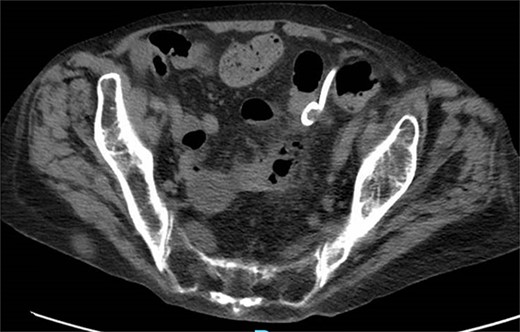

A 65-year-old female with a history of hyperlipidemia, hypertension, hip replacement, lumbar spinal fusion, chronic pain management, and prior laparotomy for endometriosis presented with a 3-day history of nausea, vomiting, and abdominal pain. She had no prior history of diverticulosis or colonoscopy. On examination, she was afebrile and hemodynamically stable. Physical examination revealed left lower quadrant tenderness, swelling, erythema, and fluctuance, suggesting an abdominal wall abscess (Figs 1 and 2). Laboratory tests showed leukocytosis with a count of 24.6 and a positive urinalysis with 2+ leukocytes. A CT scan of the abdomen and pelvis revealed a 3.8 × 3.6 cm air and fluid pocket in the low left anterior abdominal wall, indicative of an abscess likely at the site of a previous drain (Fig. 3). Additionally, there was a 2.8 × 1.8 cm irregular air pocket in the left pelvis, where an abscess had been identified in prior imaging.

CT from readmission with anterior abdominal wall abscess and left pelvic abscess.